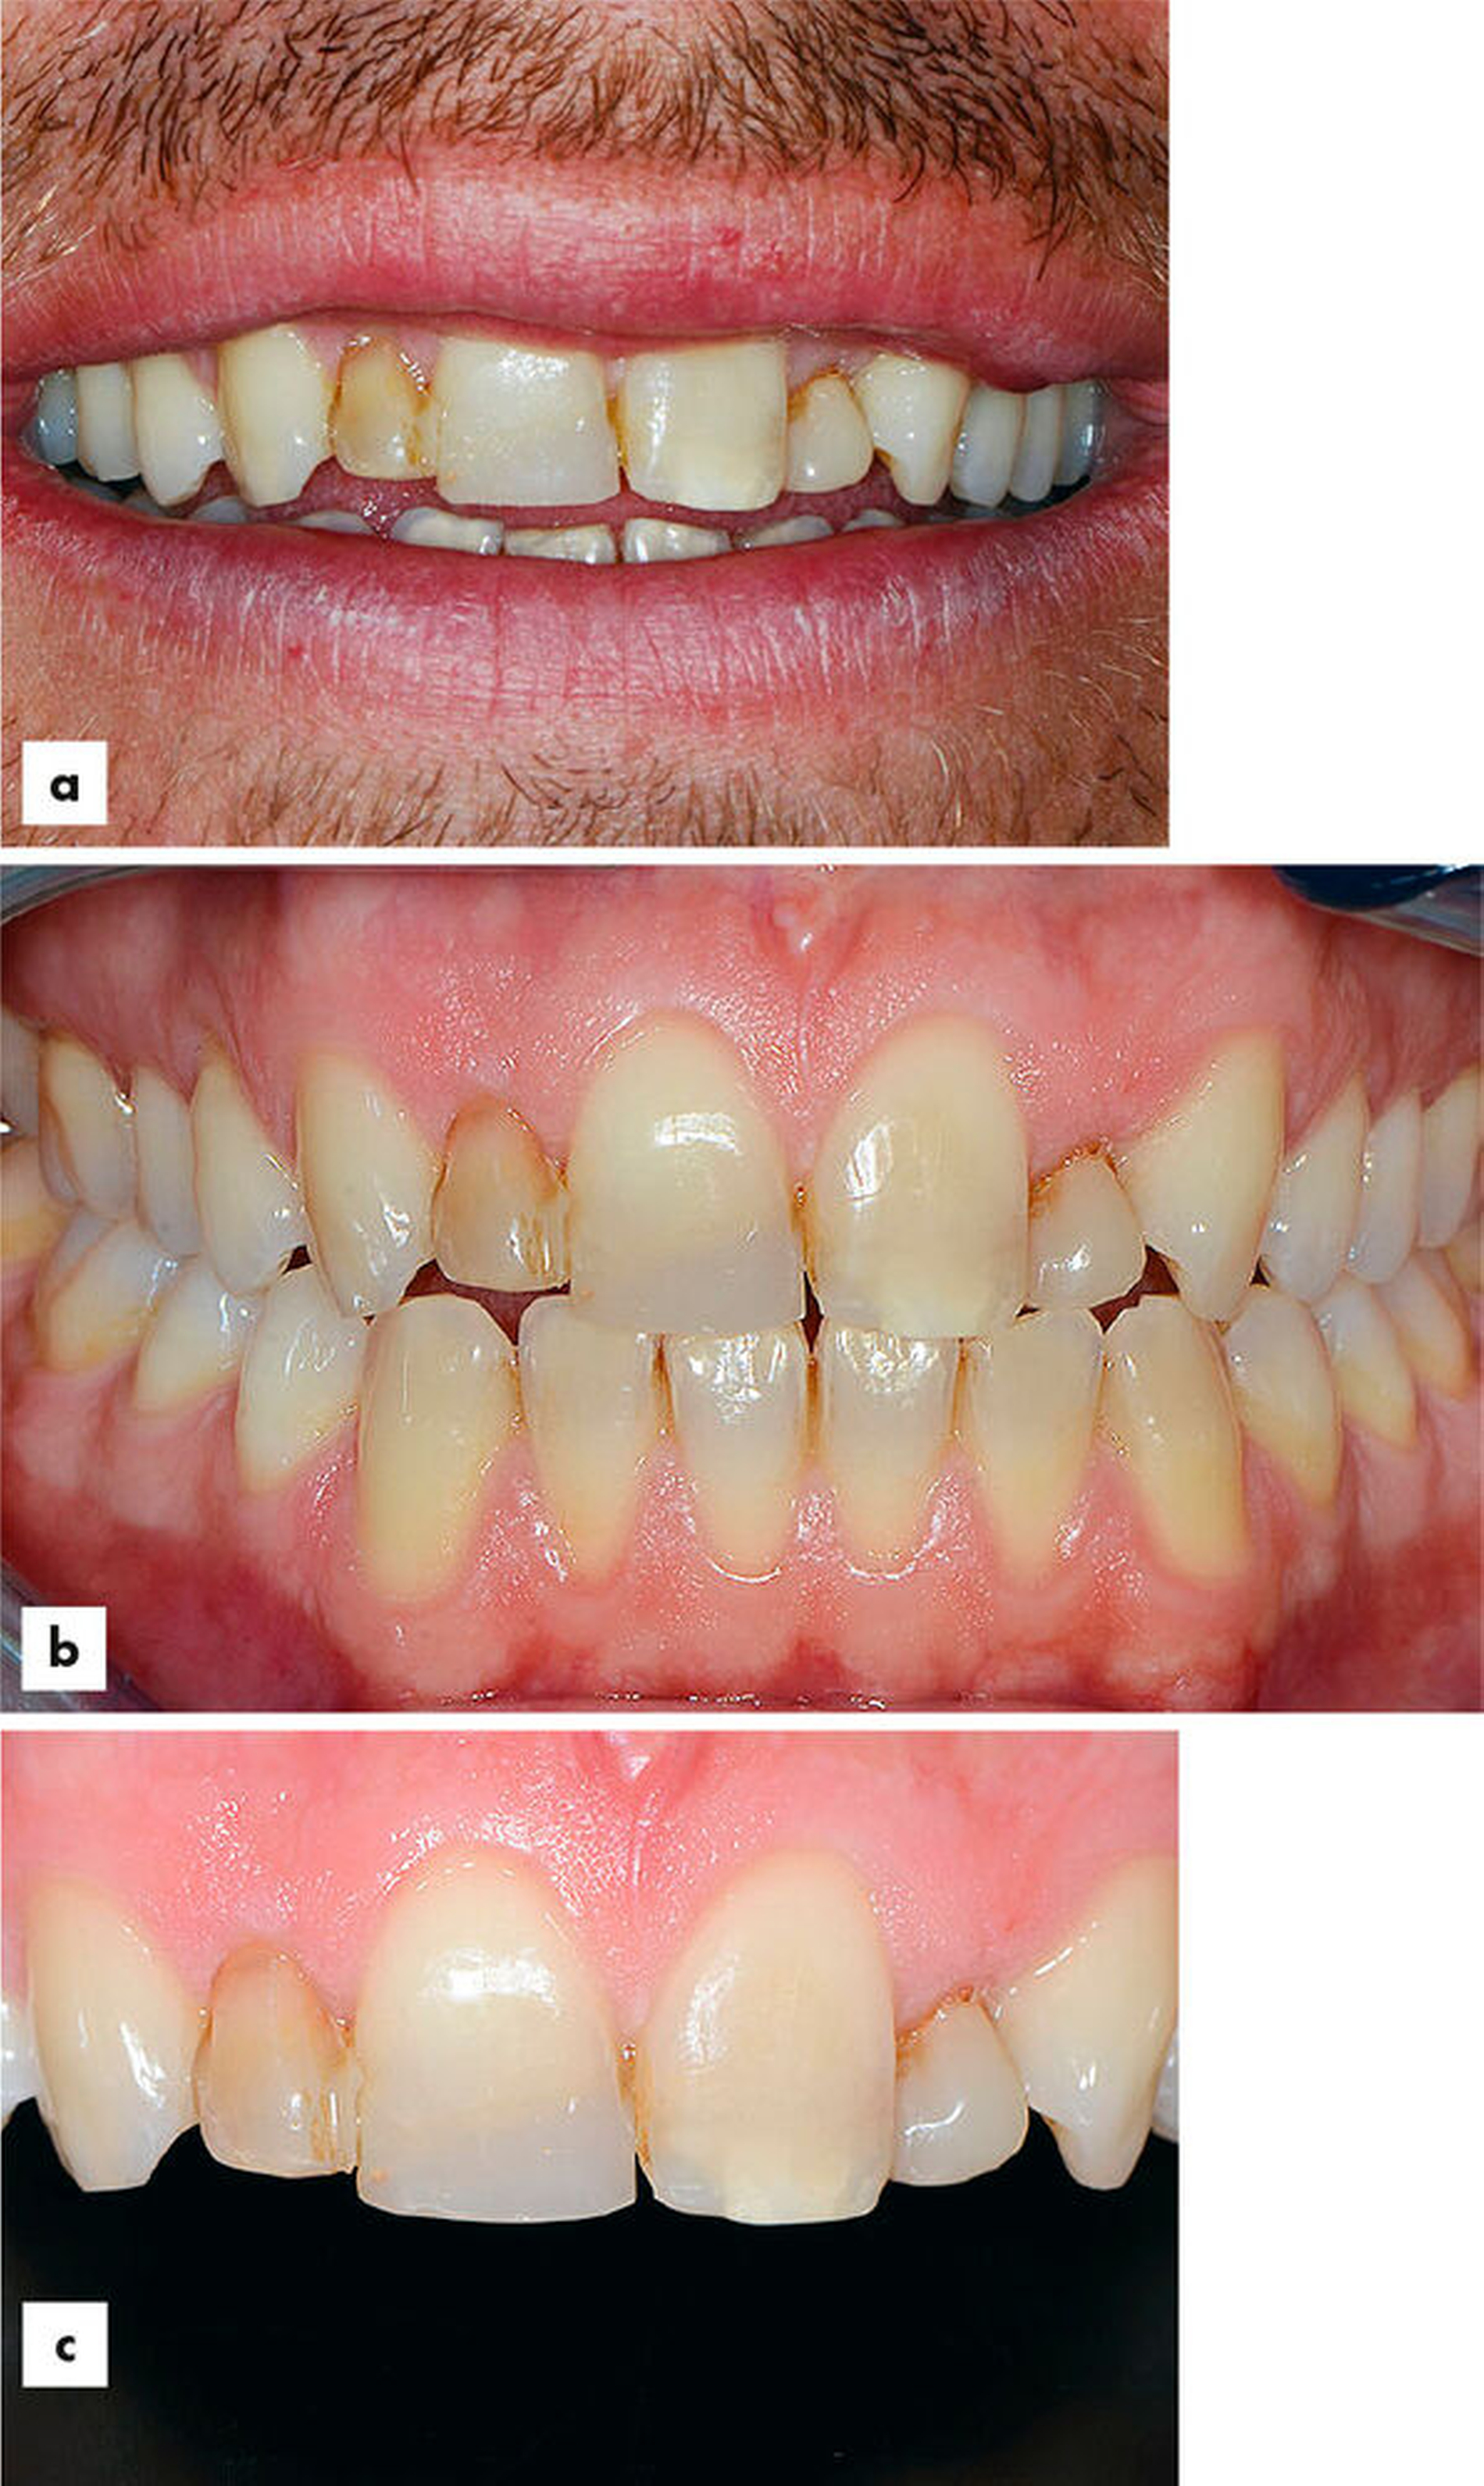

Die Abbildungen 4a–4c zeigen den Ausgangsbefund einer damals 13-jährigen Patientin nach traumatischem Verlust des Zahns 11. Aufgrund des jungen Alters der Patientin war seinerzeit eine einflügelige faserverstärkte Kompositbrücke zum Ersatz des Zahns 11 eingebracht worden. Nach sieben Jahren befindet sich die Brücke ohne Komplikationen (Fraktur, Verlust et cetera) in situ. Die Patientin ist mit dem Erscheinungsbild sehr zufrieden, es liegen keine erhöhten Sondierungstiefen am Pfeilerzahn vor und es besteht kein erhöhter Lockerungsgrad (Abbildungen 4d–4f).